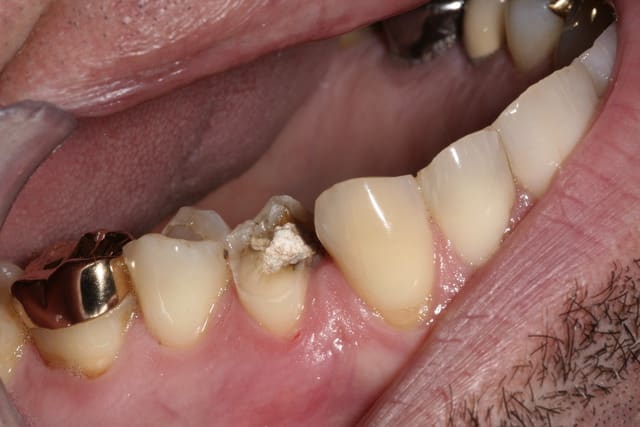

R29 uvltlt - Eugenol

R49 enunsh - Eugenol

R22 vkd0tr - Eugenol

R23 pmkimv - Eugenol

R26 gr1kkt - Eugenol

R34 w9wpow - Eugenol

Img 0052 dkvbyu - Eugenol

Leandro

28/02/2013 à 21h54

Joli travail!